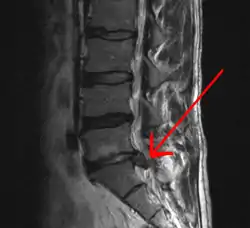

當出現上述所提的危險徵象、持續的神經學症狀、持續或越來越嚴重的疼痛時,建議做影像學檢查[5],尤其是當懷疑是癌症、感染或脊髓馬尾症候群時,最好能盡早做電腦斷層或核磁共振等影像檢查[5]。核磁共振比起電腦斷層更能偵測到椎間盤的病變,但兩者對於檢查脊椎腔狹窄都很有用[5]。至於身體檢查方面,只有少數幾個檢查項目比較有用[5],其中「抬腳測試」在椎間盤突出時幾乎都會呈現陽性反應(病患腳被抬起時會覺得疼痛)。利用脊神經阻斷術或可找到造成長期劇烈疼痛的椎間盤[42]。類似的概念如神經傳導阻斷療法也可以確認特定背痛的來源[5],有些證據顯示將麻醉藥注入小面關節/關節突間關節(英語:)、薦髂關節(英語:)以阻斷神經可能是有用的診斷方法[5]。

背痛是病患求診最常見的原因[13][43]。幾周內的疼痛常會自己好[44],因此若沒有從病患的病史或身體檢查之中找到特定背痛原因的話,一般不建議進一步做影像檢查,包括X光、電腦斷層、核磁共振[43]。很多病患會要求影像檢查,但除非有「危險徵象」[14][45],否則非必要之醫療服務[13][44]。常規做影像檢查除了會增加成本外,也會增加可能沒有益處的手術比率[46][47],且影像檢查帶來的輻射劑量對人體健康也有害處[46]。事實上,從影像檢查中找出背痛原因的比率小於1%[13],而影像也可能顯示出對健康沒有影響的異常,而這些異常即使無害,有時仍造成病人擔心甚至會要求接受進一步的治療[13]。即便如此,腰椎的核磁共振檢查總量從1994到2006年來成長了300%[15]。